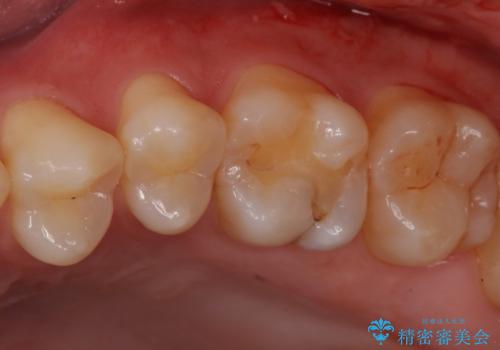

奥歯に隠れた虫歯 セラミックインレーでの修復

- 症状はないが、虫歯があれば治療をしてほしいとのことで来院。

検査の結果、昔治療した樹脂の詰め物と歯の間に虫歯ができていることが確認されました(二次う蝕といいます)。

視診だけではわかりづらいですが、レントゲン画像にて昔の詰め物の下に虫歯があることがわかります。